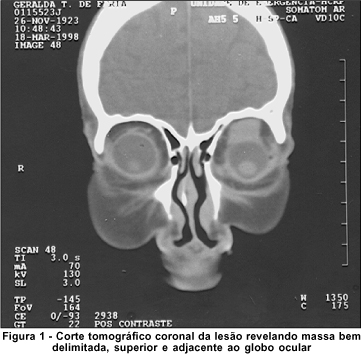

A tomografia de órbita revelou estrutura ovalada, de contornos regulares, medindo 2,0 cm x 1,2 cm, na órbita anterior e superior provocando afinamento do teto orbitário. Após a administração de contraste, notou-se reforço homogêneo da lesão (Figura 1).

Os exames de imagem não são patognomônicos. O padrão mais encontrado é o de uma lesão bem delimitada, que pode realçar com o uso de contrastes. Pode ser encontrada em qualquer lugar da órbita, mas tem predileção pela órbita superior, deslocando o olho para baixo. A histologia é fundamental para o diagnóstico(3). Em relação à evolução, os hemangiopericitomas podem apresentar comportamento benigno ou maligno. No último caso, podem gerar metástases para órgãos distantes, como pulmão, osso e fígado, e levar a óbito(4).